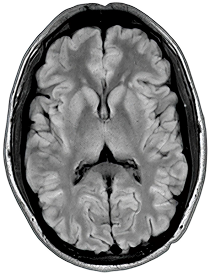

3D FLAIR

1.5T

1 x 1 x 3mm

3:31

0.5T

3:15